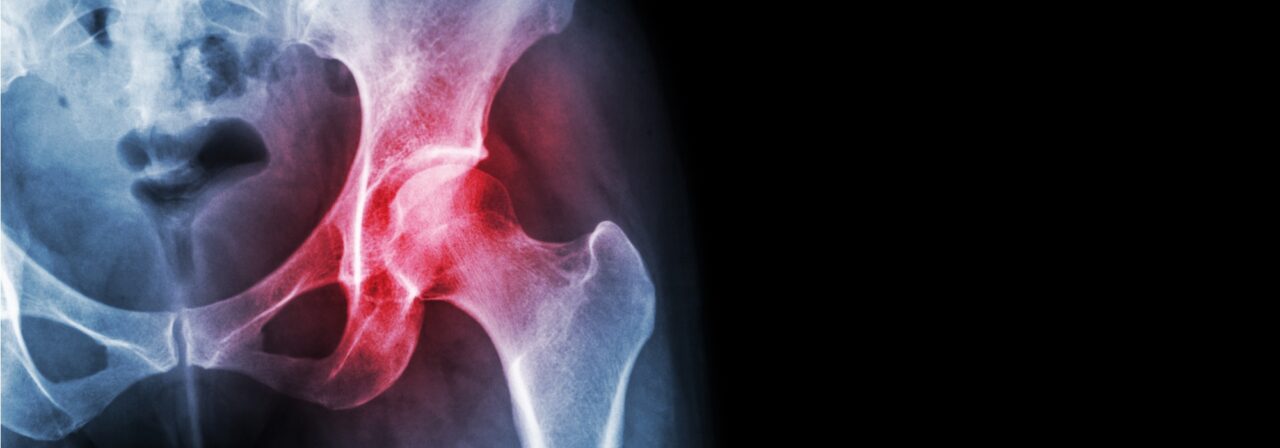

If you experience pain in any of your joints due to physical activities such as walking, running, and climbing stairs, it may be time to have a Rothman Orthopaedic Institute specialists diagnose your case. Joint replacement may be the answer for you. When simply sitting in a favorite chair or sleeping in your bed causes enough pain to wake you or make your life extremely uncomfortable, joint replacement may be able to get you back to an active lifestyle with less pain.